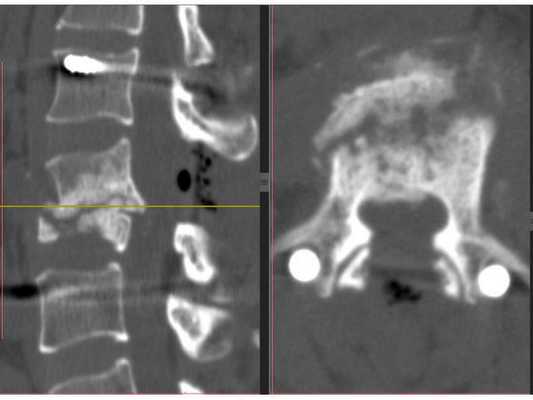

Функциональная спондилография поясничного отдела от 12.02.2019: остеохондроз II степени; спондилоартроз; нестабильность сегментов на уровне L4-L5 и L5-S1; ретролистез — смещение L5 позвонка назад — I степени. Электронейромиография (ЭНМГ) от 12.02.2019: малоберцовые нервы в норме с обеих сторон; признаки заинтересованности корешков L4-S1 справа. Мультиспиральная компьютерная томография (МСКТ) ПКОП от 13.02.2019: КТ-картина дегенеративно-дистрофических изменений поясничного отдела позвоночника; большая задняя срединная грыжа межпозвонкового диска на уровне L4-L5 позвонков с абсолютным стенозом спинального канала; задние диффузные протрузии дисков L5-S1 и умеренная протрузия уровня L2-L3. МРТ ПКОП от 14.02.2019: МР-картина дегенеративно-дистрофических изменений сегментов ПКОП; задняя медианная экструзия (выбухание) диска L4-L5 с признаками компрессии корешков конского хвоста и вторичного дурального стеноза на уровне L4-L5 на 2/3; протрузии дисков L2-L3 и L5-S1; ретролистез L5 I степени.

Диагноз

Остеохондроз пояснично-крестцового отдела позвоночника. Дискогенная радикулопатия L5 справа, обусловленная секвестрированной парамедианной транслигаментарной грыжей диска L4-L5 с компрессией L5 корешка и абсолютным стенозом позвоночного канала. Выраженный стойкий болевой и миотонический синдром.